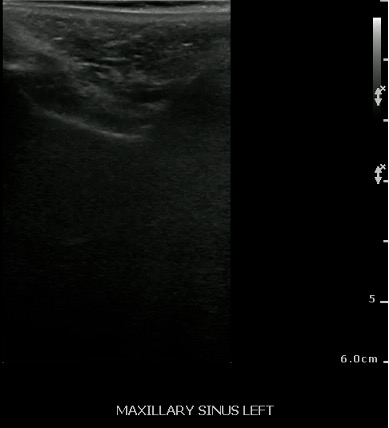

- Normal Maxillary Sinus:

- The normally air-filled maxillary sinus prevents the transmission of ultrasound beams (Air reflects most of the signal, thus preventing visualization of deep structures).

- The anterior maxillary sinus wall produces a bright echo in the near field, with reverberation artifact posteriorly (producing a snowstorm appearance), and preventing visualization of the posterior wall.

- Figure 27 and 28. Normal maxillary sinus

Video 19. Normal Maxillary Sinus